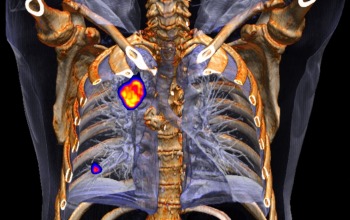

PET-Aufnahmen ohne Stopp liefern präzisere Bilder

Der Biograph mCT Flow kombiniert zwei bildgebende Verfahren, nämlich die Computertomographie und die Positronen-Emissions-Tomographie (PET). Die…